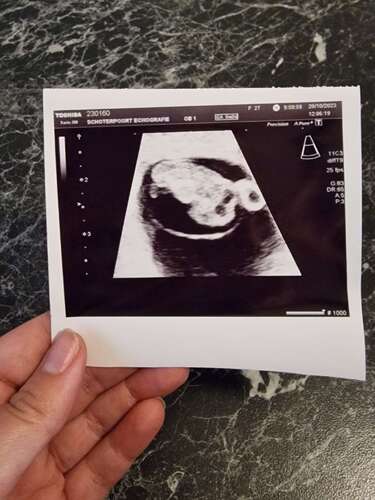

Gisteren 31-10-23 , 6+6 weken. Ons wondertje 🥰